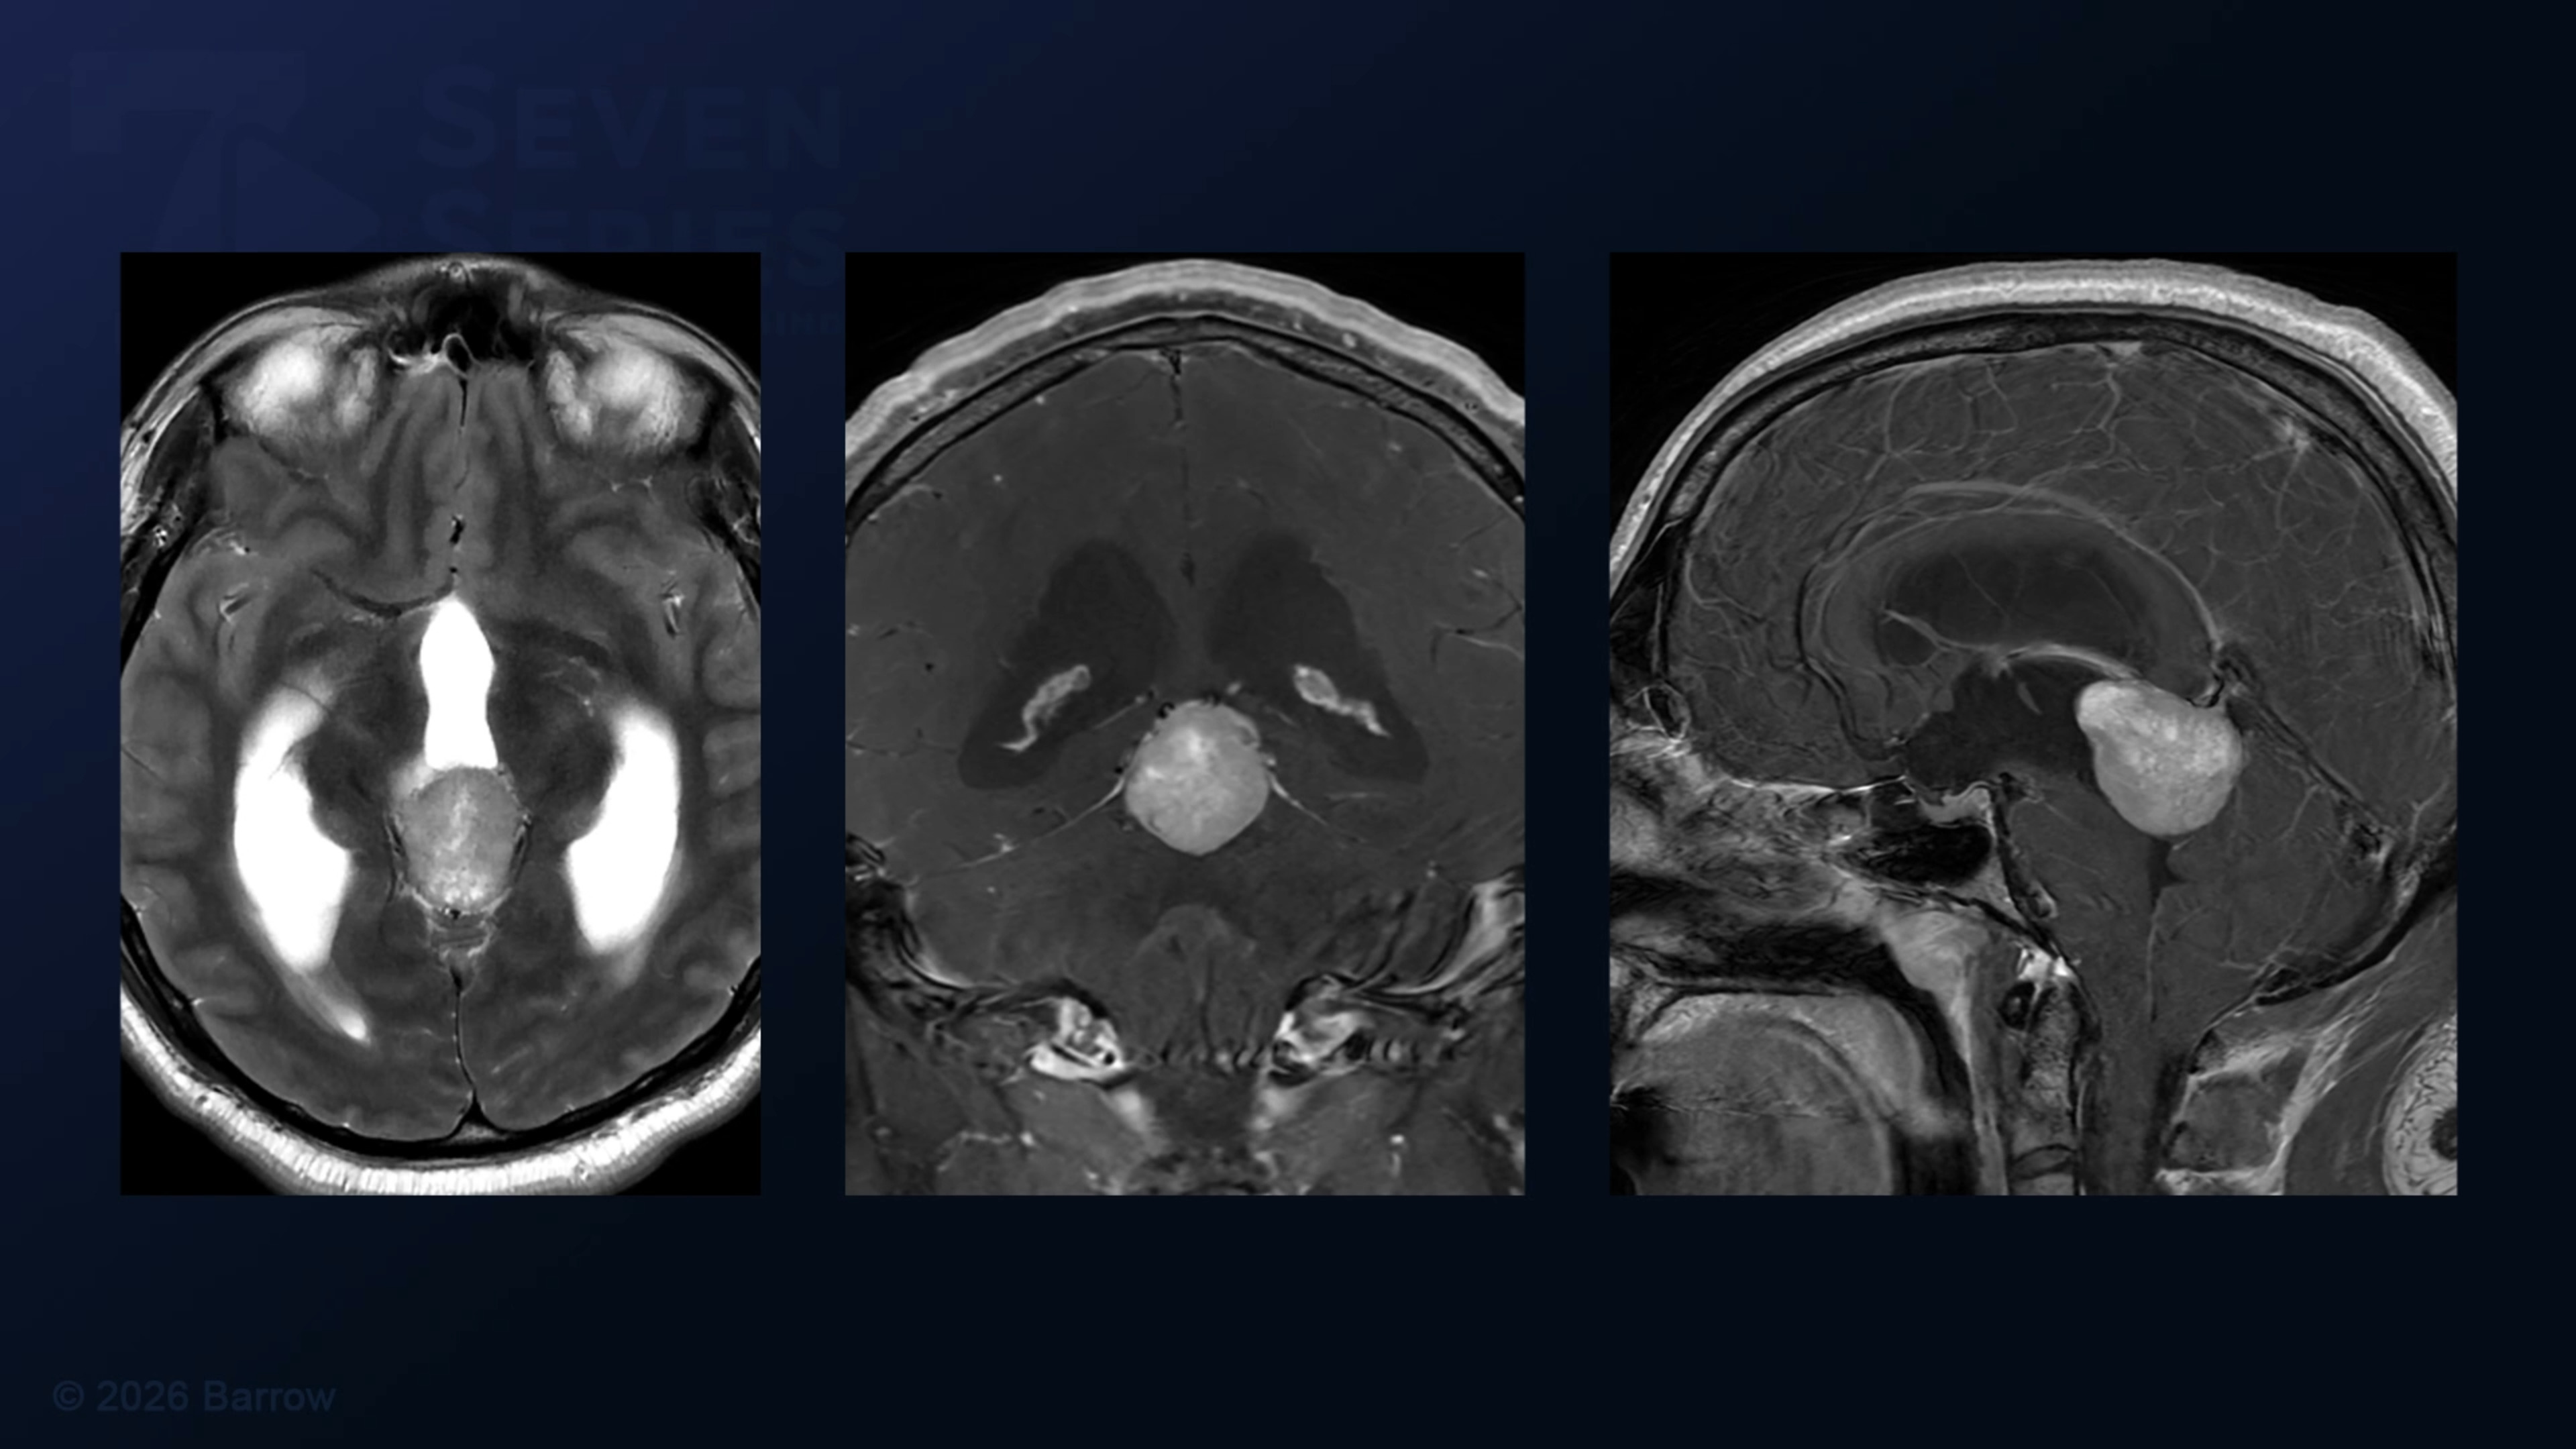

#513: Torcular Craniotomy and Supracerebellar Infratentorial Approach for Resection of a Large Pineal Tumor

Episode 513 of Seven Series shows a torcular craniotomy and supracerebellar infratentorial approach for resection of a large pineal tumor.